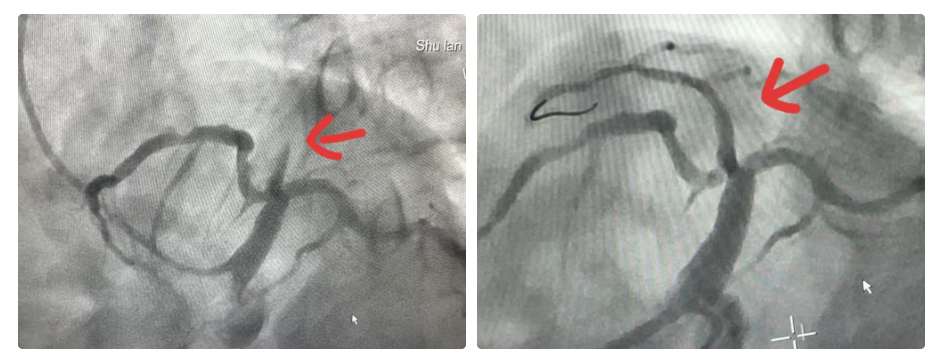

井大爷既往存在高血压并控制不佳、大量吸烟史,是心肌梗死的高危人群,且年龄偏大,手术风险徒增。术中造影显示中间支近中段完全闭塞、钙化严重,为支架的置入增加了难度。心血管内科介入团队崔连群主任、邱洁副主任医师迎难而上,迅速将导丝通过闭塞血管,抽吸局部血栓,球囊扩张钙化病变、打通闭塞的血管、置入支架,整个手术过程娴熟、精准。随着阻塞血管血流的恢复,井大爷疼痛迅速缓解,心电图抬高的ST段明显回落,相关心肌损伤标记物存在明显高峰前移,生命体征也趋于平稳。